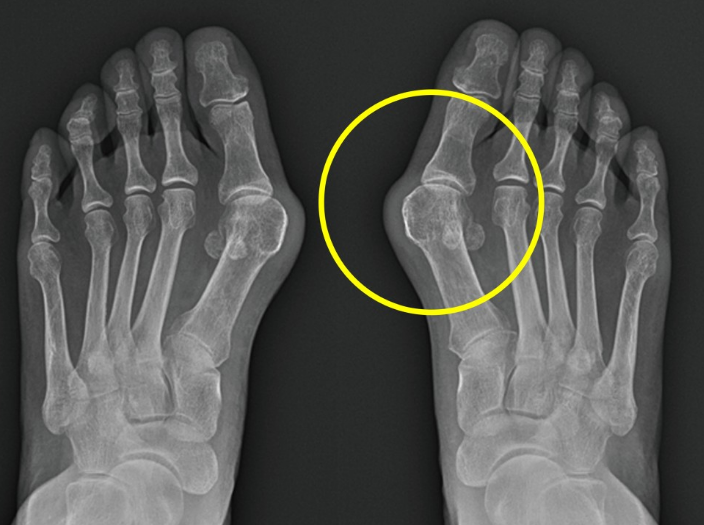

수술적 치료 방법은 증상과 정도에 따라 여러 가지 방법을 선택할 수 있습니다. 가장 대표적인 수술은 문제가 되는 엄지발가락 쪽의 제1중족골을 절골, 즉 부러뜨려서 이동시킨 뒤에 금속 나사 등으로 고정하는 방법입니다. 전통적으로 안쪽 피부 절개를 하여 수술을 시행했으나 최근에는 절개를 최소화 한 최소침습 무지외반 교정술 방법이 알려져 있어 환자들의 수술 후 회복이 매우 빨라졌습니다. 무지외반증으로 고생하고 있는 분들이 있다면 정확한 진단과 치료 방법에 대하여 정형외과 전문의와 상의하길 권장합니다